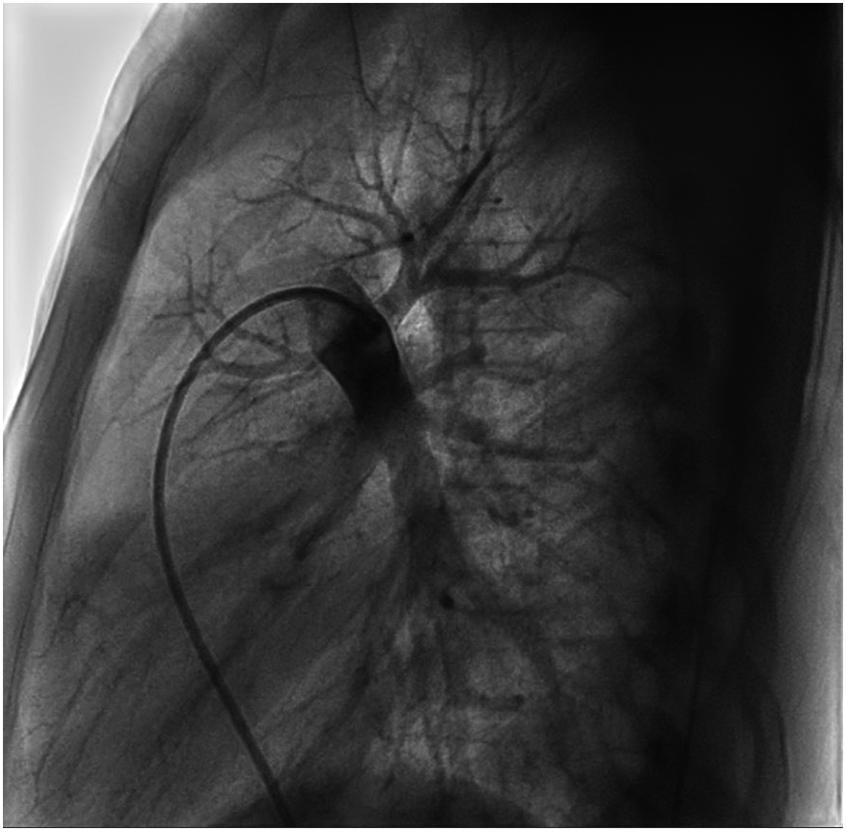

We performed a detailed evaluation of the cardiovascular system, including tests for right-to-left diverged heart disease, pulmonary arteriovenous fistula, severe valve regurgitation, and pulmonary hypertension.After conducting detailed echocardiography and cardiac CTA, we performed cardiac catheterization. The results of cardiac catheterization were negative. Cardiac catheterization findings are shown in Figures 3–6. We were unable to find a shunt at the atrial, ventricular, or aortic levels. The child's echocardiogram and cardiac macrovascular CT results were normal, ruling out complex congenital heart disease such as pulmonary atresia.

Figure 3

Frontal and lateral views of the child's left pulmonary arteriogram.

Figure 4

Figure 5

Frontal views of the child's right pulmonary arteriogram. No pulmonary arteriovenous fistula was found.

Figure 6